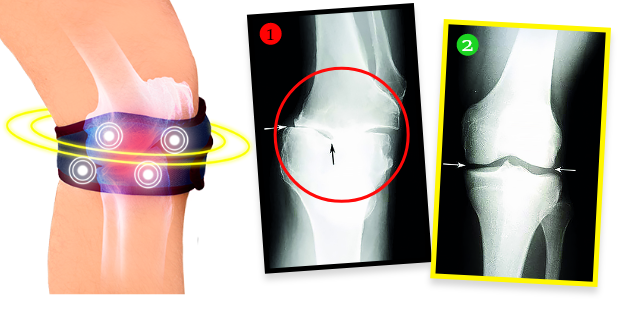

Gospa Helena je po tretmaju naredila rentgensko sliko in izkazalo se je, da so bile degenerativne spremembe v kolenu popolnoma odstranjene! Zdravnik je bil osupel – ni vedel, kaj naj reče. In dejstvo je, da se zaradi biomagnetnega traku Helenino stanje kolena ni samo nehalo slabšati. Hrustanec in občutljive strukture v sklepu so se regenerirale, kolenu pa se je vrnila funkcionalnost kot pred leti. Trak oddaja naravno in varno biomagnetno polje, ki prodira v najgloblja tkiva sklepa, hrani in obnavlja hrustanec, obnavlja njegovo elastičnost in odpornost ter spodbuja nastajanje sinovialne tekočine, ki med gibanjem blaži in ščiti pred bolečim trenjem. Gre za popolnoma neinvazivno in varno terapijo.

"Še en mesec nazaj sem imel uničene, škripajoče sklepe, zaradi česar sem komaj hodil. Vsak večji fizični napor je povzročil, da so sklepi eksplodirali od bolečin. Zahvaljujoč temu traku imam občutek, da so moji sklepi tako funkcionalni kot pri najstniku! To potrjujejo rezultati kontrolnih rentgenskih slikanj, ultrazvoka in magnetne rezonance. Ko sem jih zagledal, sem zajokal od sreče. Kdo pa ne bi jokal? Moja kolena so kot nova!"